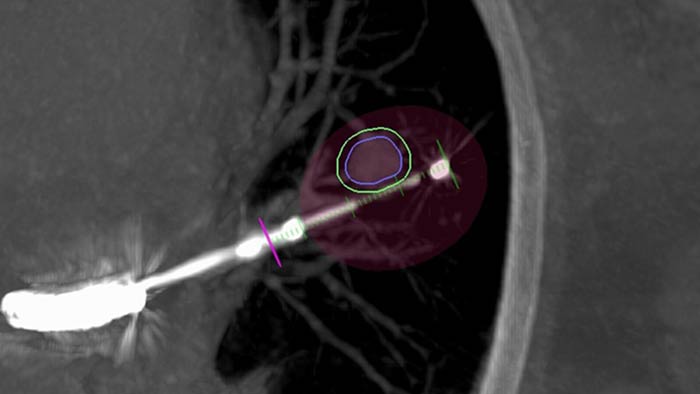

Planning and guidance for percutaneous biopsy, marking and ablative therapy.